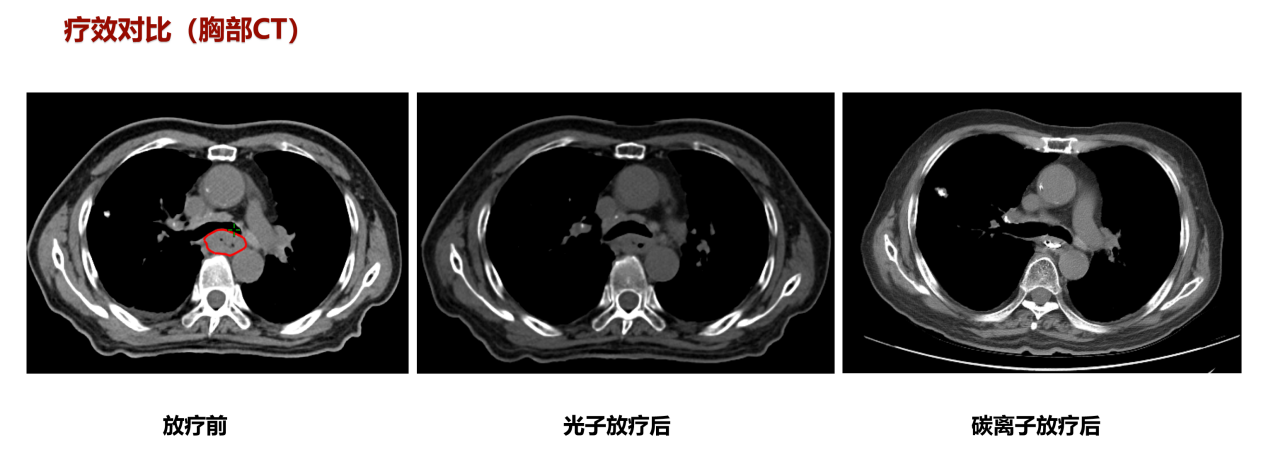

患者苏某某,男,73岁。2022年2月患者无明显诱因出现进食不畅,进行性加重。查上消化道造影示:食管中段癌(髓质型)。胃镜示:食管距门齿26cm可见向腔内环周生长的肿物,表面溃疡、糜烂、质脆易出血。镜下活检后病理示:(食管)鳞状细胞癌。诊断:1、食管恶性肿瘤(中段 髓质型 鳞状细胞癌 cT3N2M0 III期 KPS评分: 90分 2、冠状动脉硬化性心脏病(心脏支架置入术后)。治疗计划:同步放化疗【1、放疗(光子+碳离子),2、化疗:卡培他滨单药口服化疗】。放疗剂量:光子VMAT技术PTV2 2Gy×20F=40Gy,碳离子PTV1 4Gy(RBE)×4F,总56Gy。

该患者放疗后进食哽噎较前明显好转,放疗后复查胸部CT提示:现胸中下段食管管壁增厚并强化、管腔变窄,病变局部与邻近结构分界不清,较前食管病变明显好转,临床疗效评价为PR。放疗3月后复查食管造影提示管壁通畅,行胃镜检查并取检未查见癌细胞,疗效评价为CR。【病例提供医生:李小军 科室:放疗中心一科(兰州院区)】